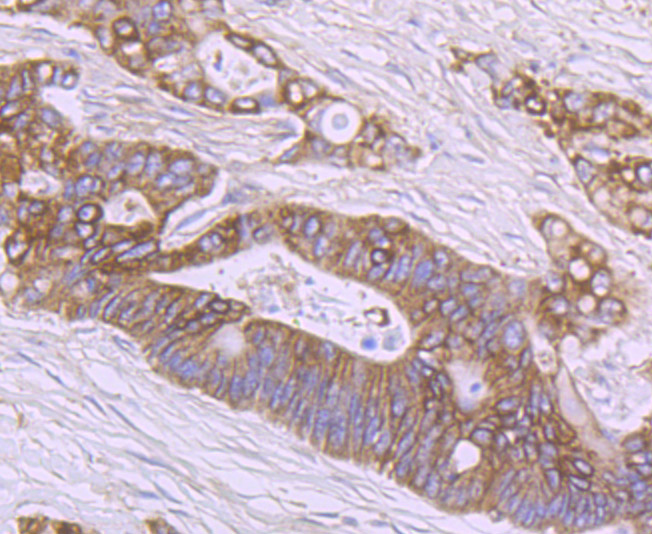

Immunohistochemical analysis of paraffin-embedded human colon cacner tissue using anti-SHP2 antibody. Counter stained with hematoxylin.